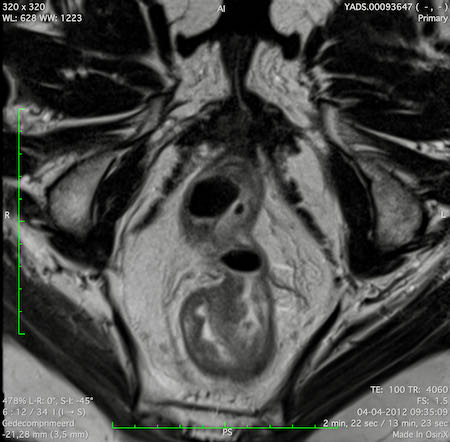

Hình ảnh

Các hình ảnh được cung cấp cho thấy ung thư biểu mô tế bào nhẫn với tình trạng dày lan tỏa thành trực tràng, hình ảnh bia bắn điển hình, và sự xâm lấn mỡ mạc treo trực tràng.